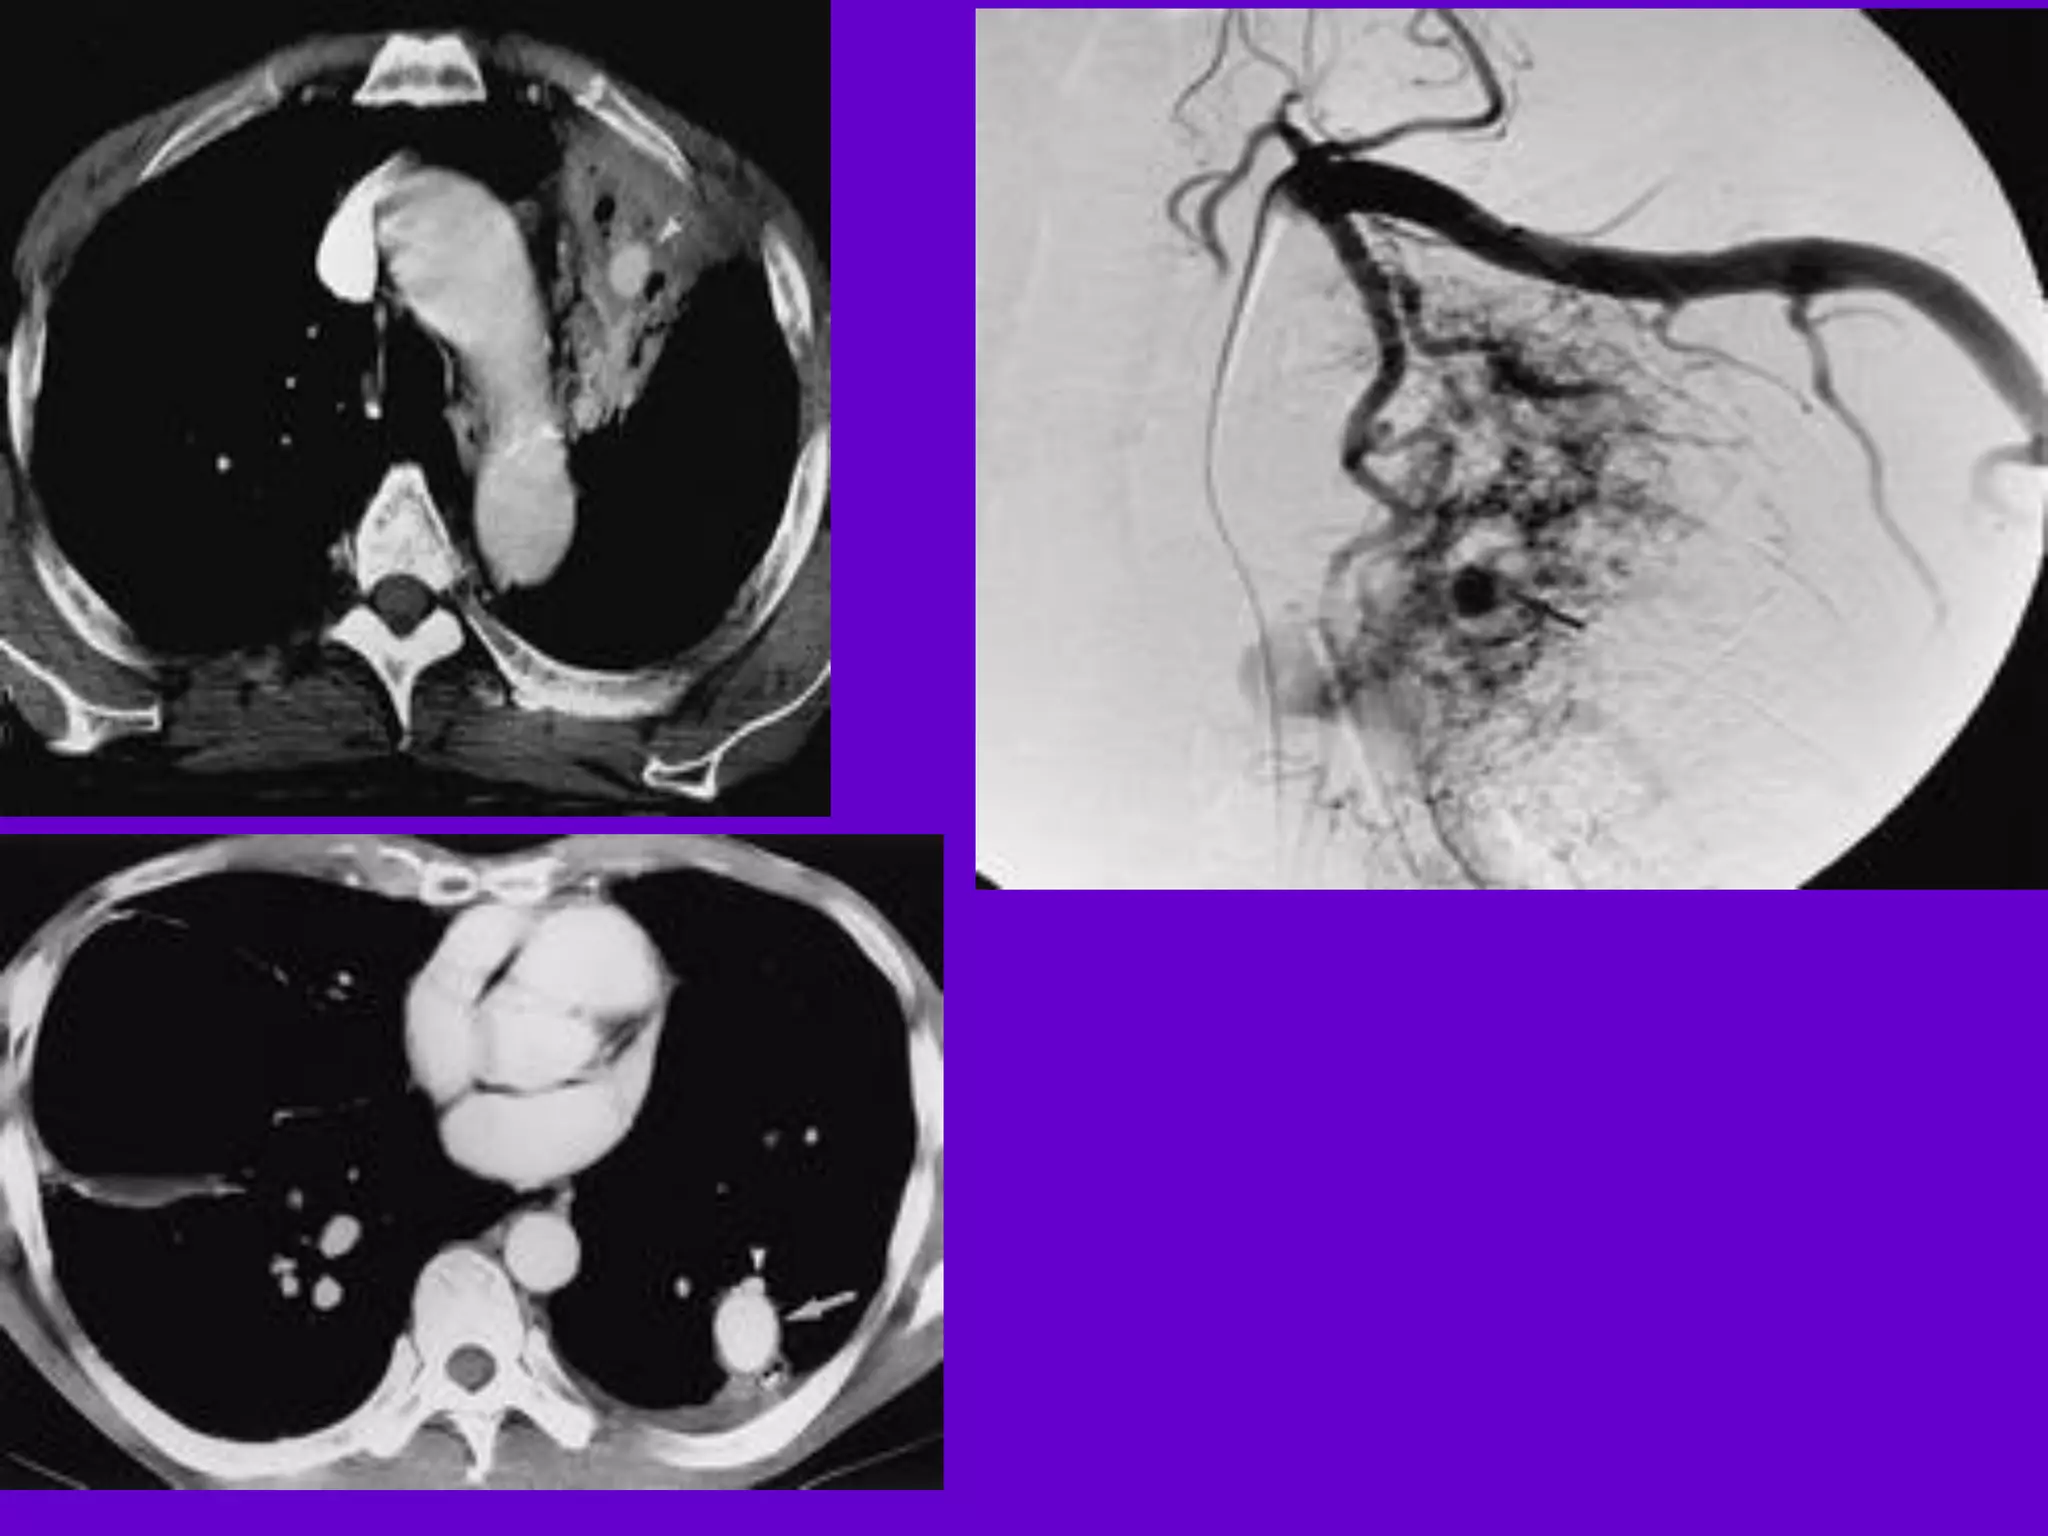

CT Scan and MRI Scan in the

diagnosis of TB

􀂄 The advent of CT and MRI imaging in

the last two

decades has redefined the approach in

analysis of

various diseases including TB.*

􀂄 CT and MRI have shown several

advantages over

conventional radiology in early diagnosis

and follow-up

of TB in different parts of the body.

*Buxi TBS Indian J Pediatr 2002;69:965-972

Pulmonary TB :

Lobar Pneumonia

􀂄

CT is superior than plain CXR in picking

up the

consolidation, atelectasis and the hilar LN

thereby

making the diagnosis easy.

􀂄 MRI reveals some of these changes,

however, CT is

the diagnostic modality of choice in such

cases.

Pleural Effusion 􀂄

􀂄 CT is sensitive to diagnose and define

even minimal

pleural effusion/pleural calcification.

􀂄 Pleural fluid is seen on inversion

recovery MR

images as areas of increased signal

intensity along

the inner aspects of the chest wall.